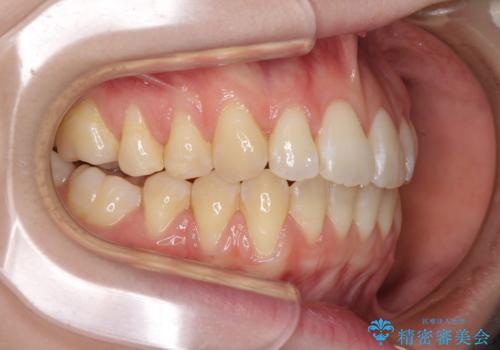

気になるデコボコとオープンバイト インビザラインでの矯正治療

- 前歯のデコボコと上下が開いていることを気にして来院された患者様です。

いわゆるオープンバイトは、インビザラインによる治療が適しているため、インビザラインにて治療を行うこととしました。

オープンバイトは容易に後戻りを起こすため、少しでも後戻りリスクを軽減するために舌癖改善のトレーニングをしっかりと行っていただきました。